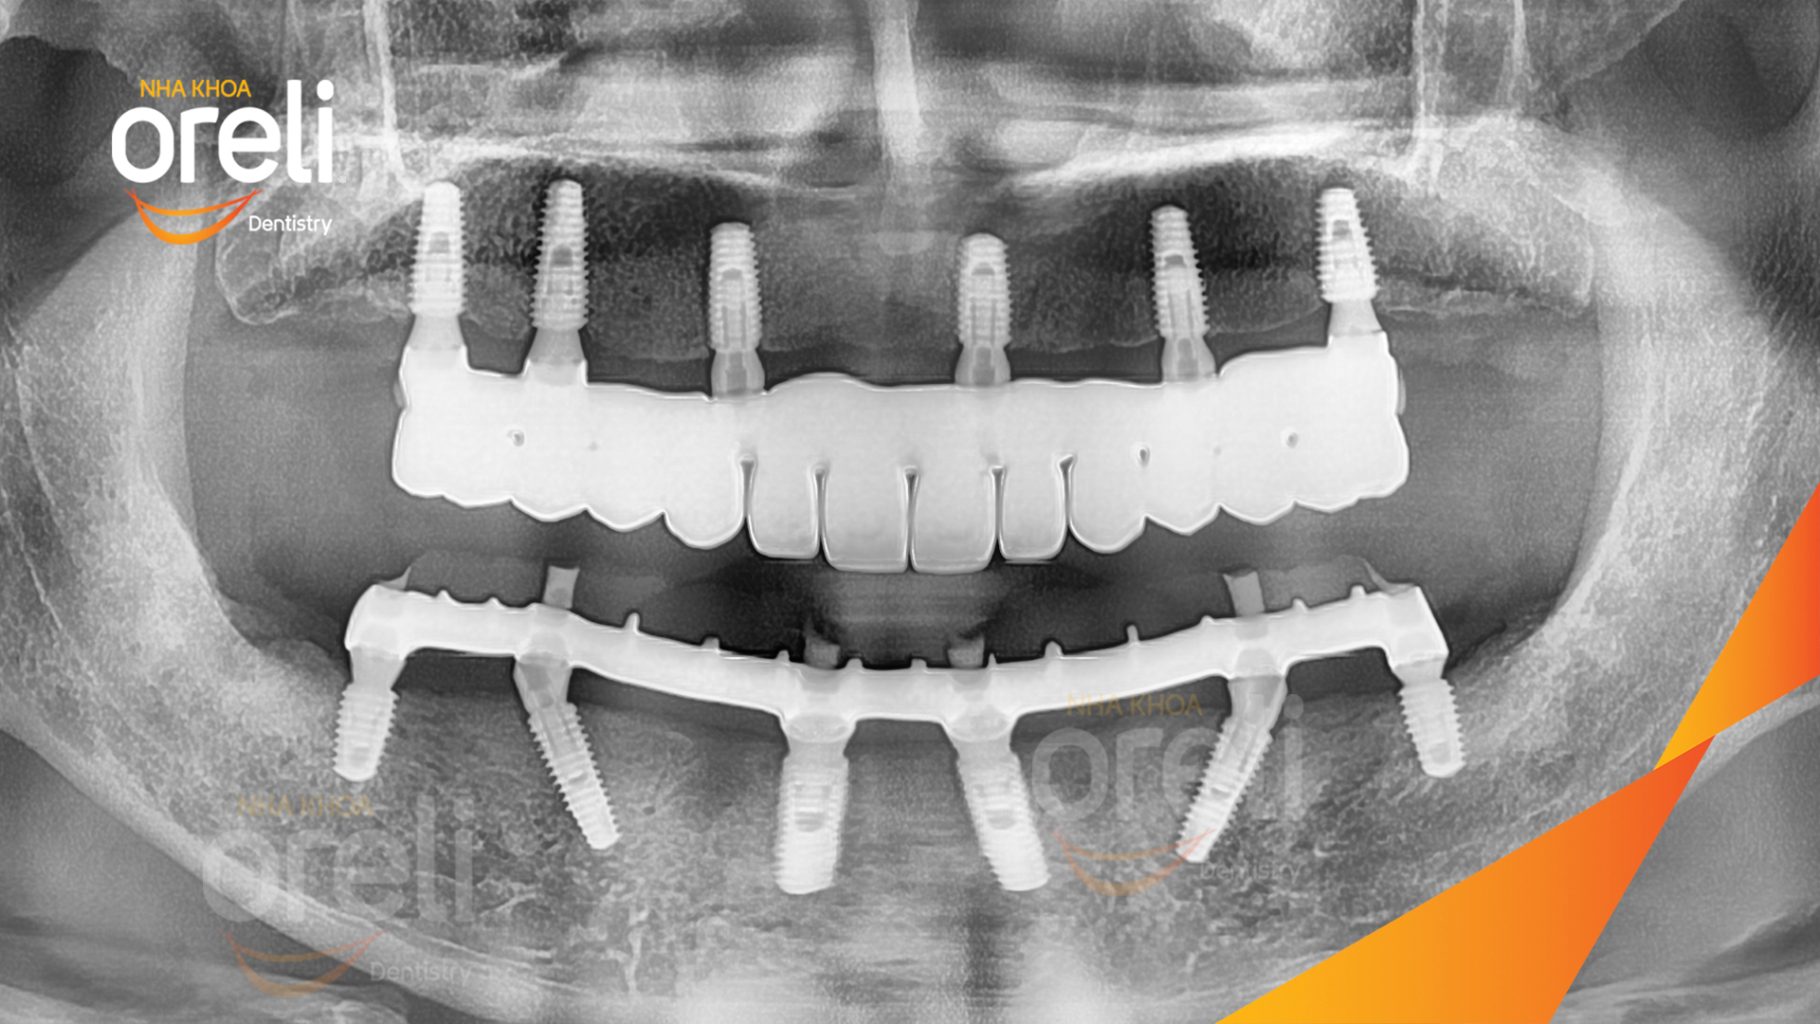

Ca trồng răng implant toàn hàm phục hồi ăn nhai và thẩm mỹ nụ cười. Kết quả thực tế trước và sau điều trị tại Nha khoa Oreli.

Tình trạng: Mất răng toàn bộ hàm trên và hàm dưới

Giải pháp: Trồng răng implant hai hàm với phục hình tạm

Hình ảnh thực tế